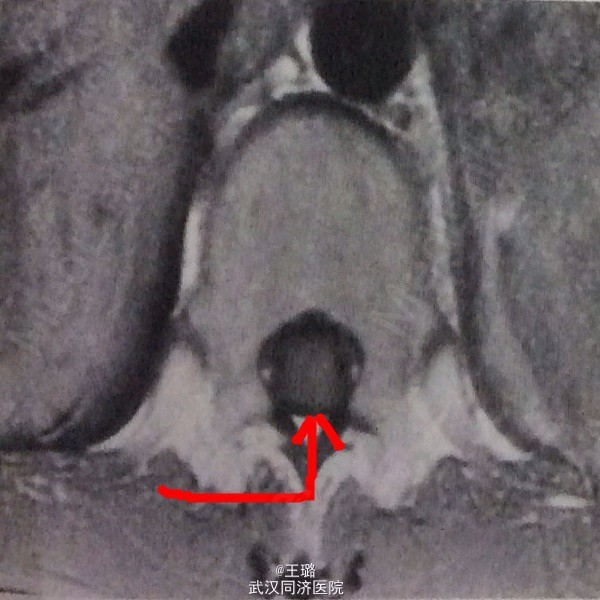

体格检查:体温38度,肺部未闻及干湿啰音,肢体肌力减低,神经反射弱,病理反射未引出。实验室检查:淋巴细胞增高,余正常。电解质、生化检查无异常。影像学检查:CT增强:病灶呈环形强化,壁厚薄较为均匀。MRI:腰段脊髓呈梭形增粗,其内见一类圆形病灶。

诊断:脊髓占位性病变待查 治疗:形脊髓腔切开切除占位性病灶,病检示:结核球,遂给予口服抗结核药物标准化治疗。一次药物鞘内注射。